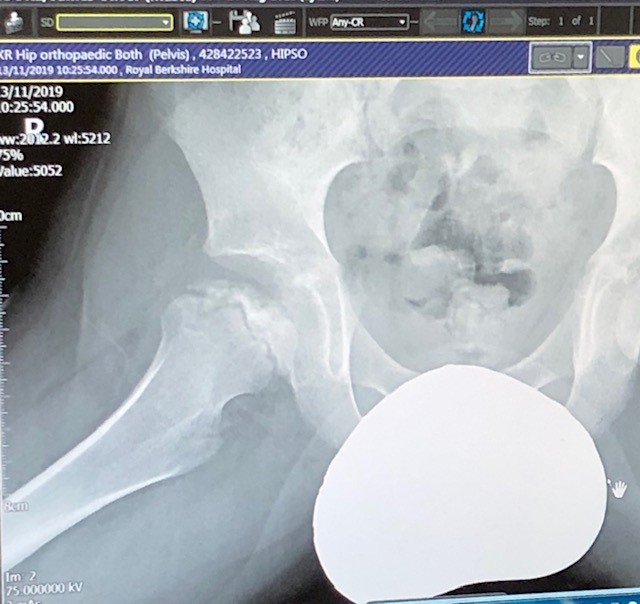

“Progress” of Perthes throughout 2019